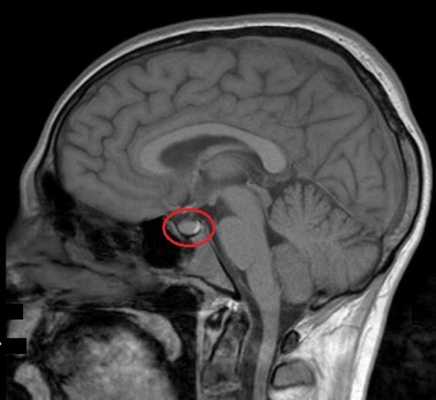

МРТ гипофиза с контрастом. После введения контрастного вещества в гипофизе происходит его накопления и он выглядит светлым. Только участок опухоли не накапливает контрастное вещество и выглятит темным (стрелка).

МРТ гипофиза с контрастом или без не требует специальной подготовки. Но на исследование стоит приходить в одежде, на которой полностью отсутствуют любые металлические детали, включая пуговицы, косточки в бюстгальтере и т. д. Поскольку чаще всего рекомендуется делать МРТ с контрастом (при условии отсутствия противопоказаний), за час до него следует отказаться от употребления пищи.